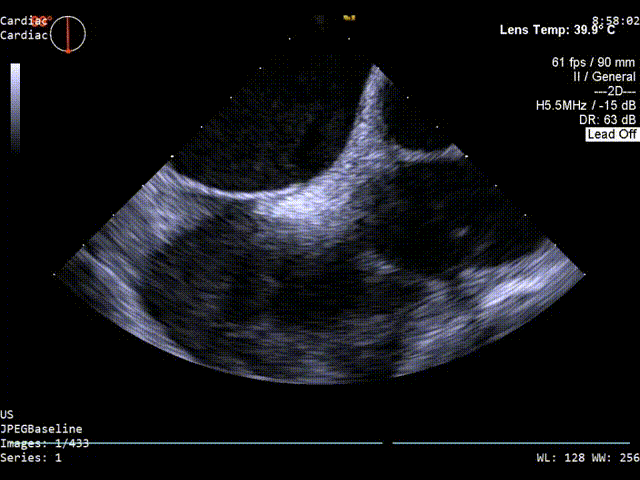

主动脉短轴切面超声影像

原发隔厚度0.84mm,继发隔厚度约:5mm;

PFO间隙2mm,隧道长度8.2mm(主动脉短轴);

1、PFO结构:静息状态下房水平见左向右分流。继发隔厚约5mm;原发隔厚约0.84mm;未探及下腔静脉残瓣及希阿里氏网。